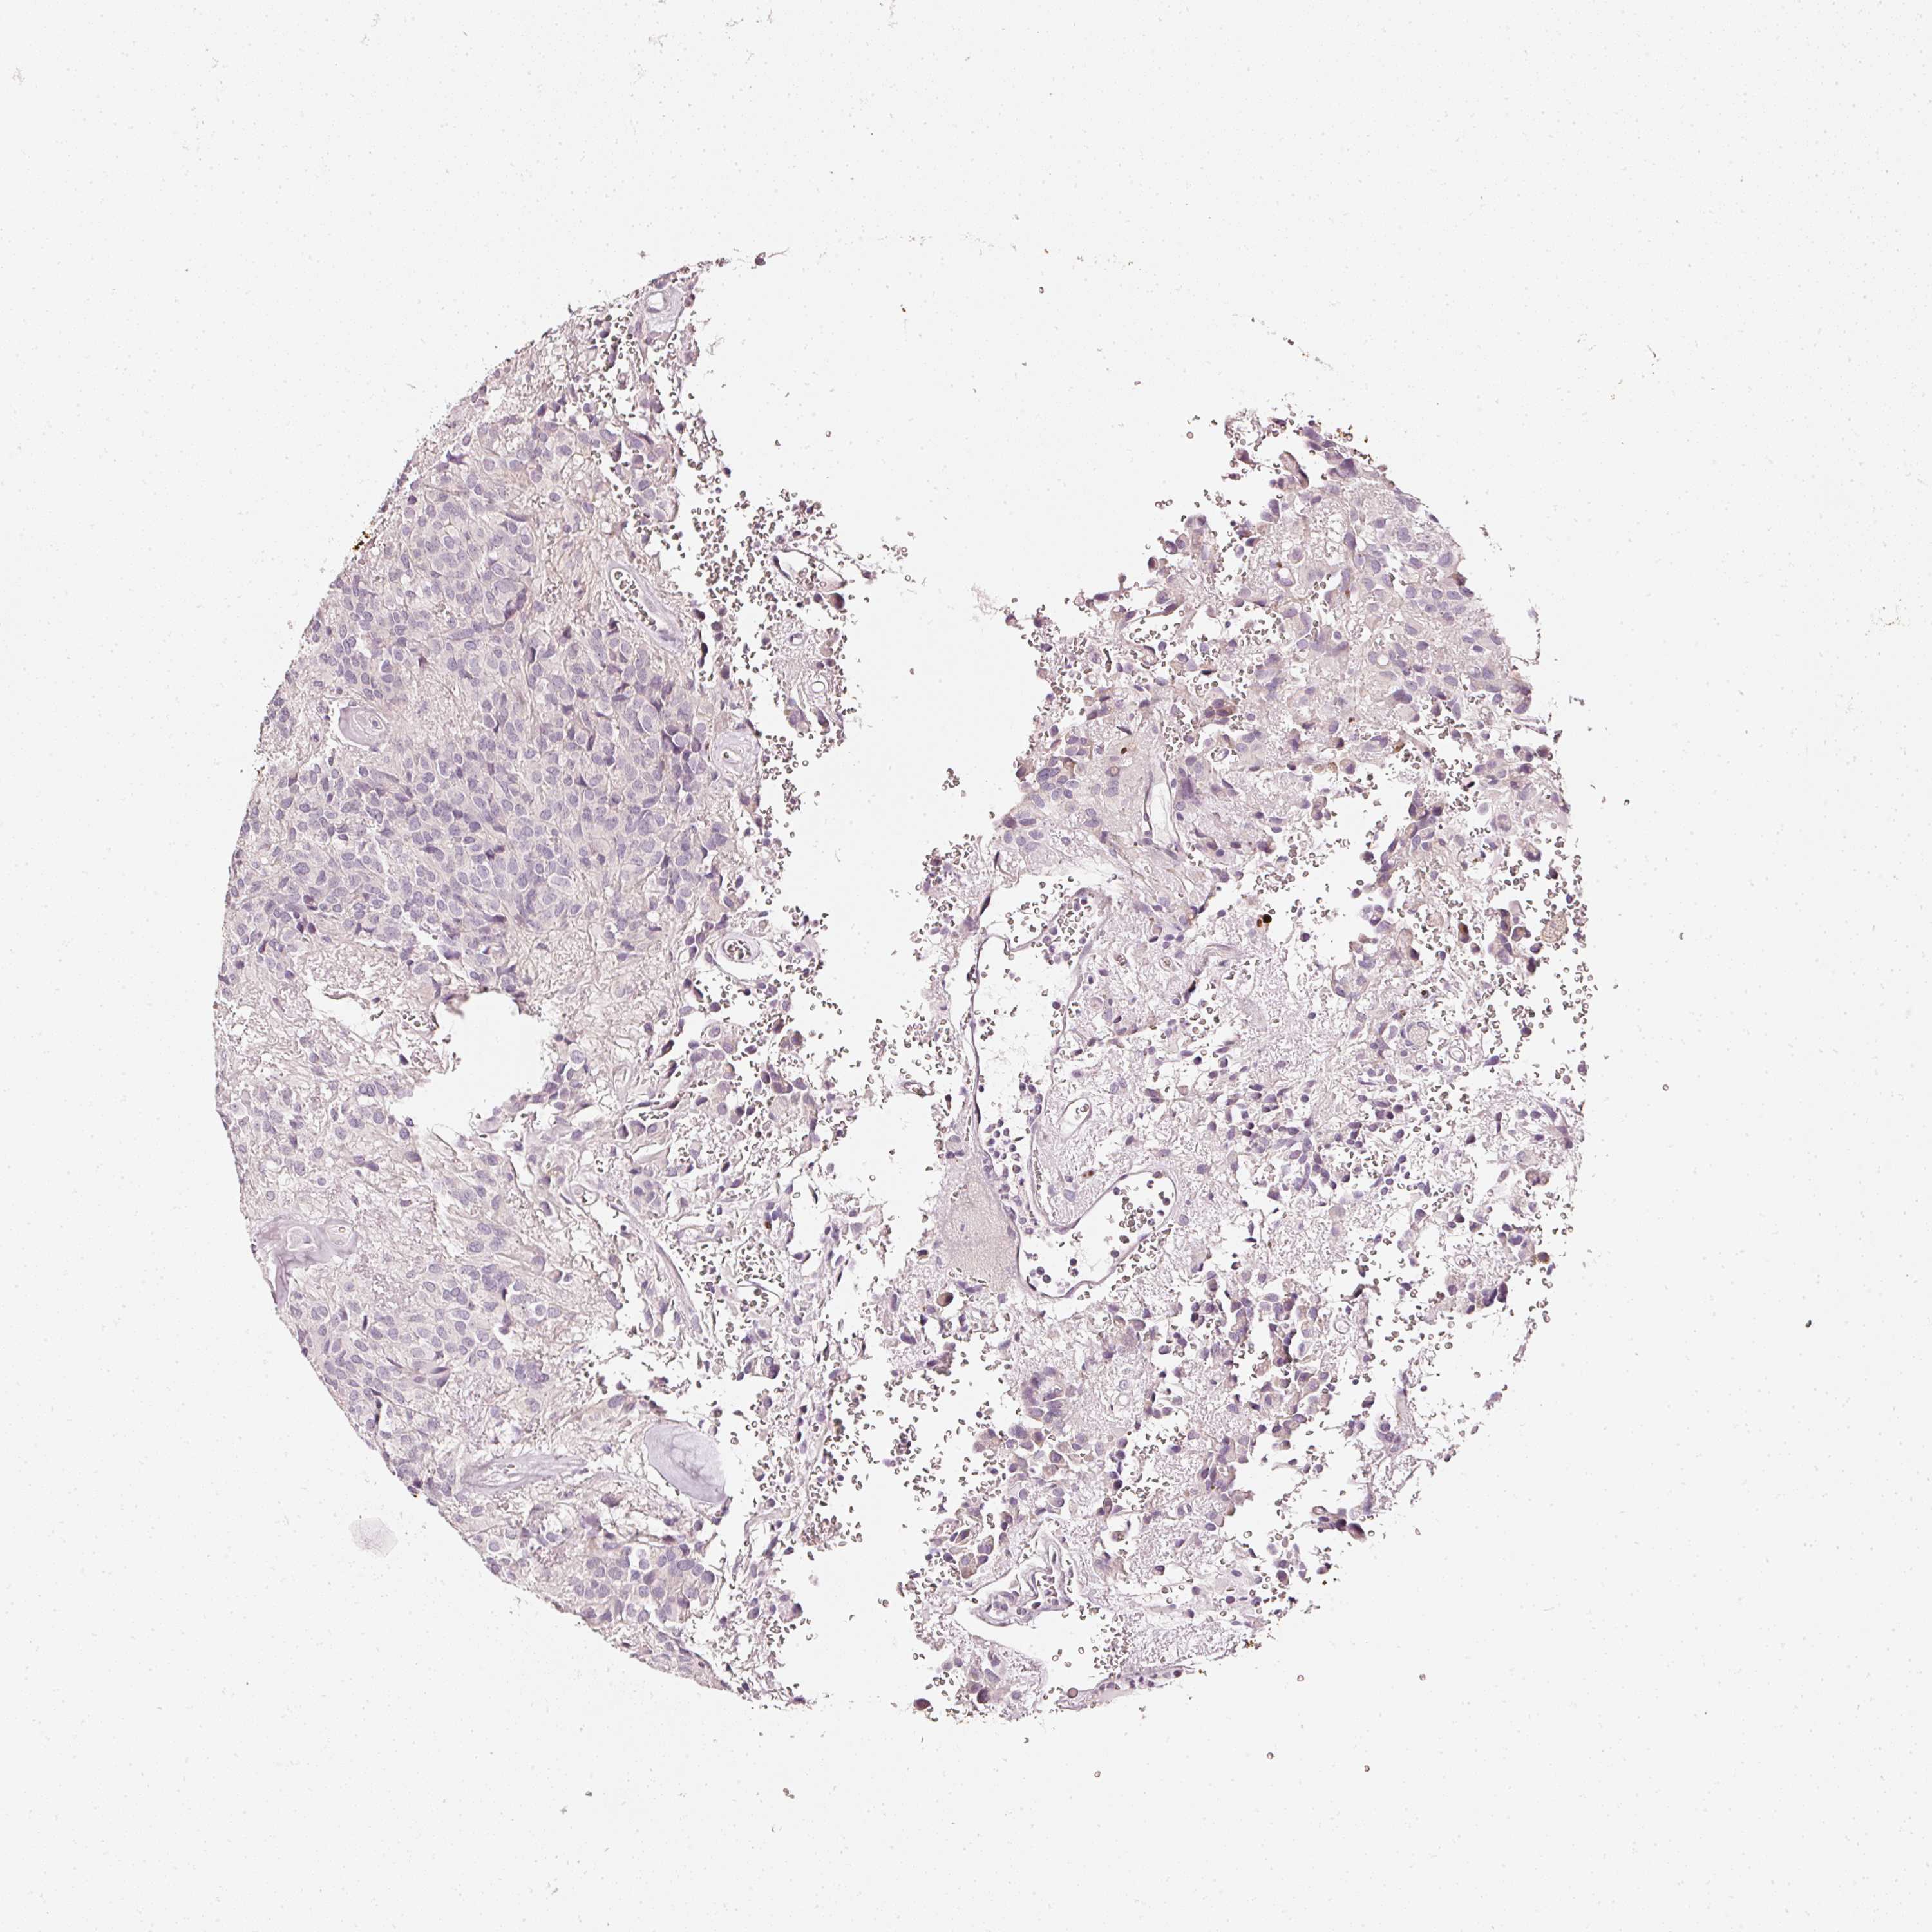

GLIOMA - Protein expressioni

A mouse-over function shows sample information and annotation data. Click on an image to view it in a full screen mode. Samples can be filtered based on level of antibody staining by selecting one or several of the following categories: high, medium, low and not detected. The assay and annotation is described here.

Note that samples used for immunohistochemistry by the Human Protein Atlas do not correspond to samples in the TCGA dataset.

Antibody stainingi

Antibody staining in the annotated cell types in the current human tissue is reported as not detected, low, medium, or high, based on conventional immunohistochemistry profiling in selected tissues. This score is based on the combination of the staining intensity and fraction of stained cells.

Each image is clickable and will lead to virtual microscopy that enables deeper exploration of all samples and also displays staining intensity scores, fraction scores and subcellular localization as well as patient and tissue information for each sample.

HPA023266

HPA023278

HPA023280

HPA023338

CAB002672

Glioma, malignant, High grade

Glioma, malignant, Low grade